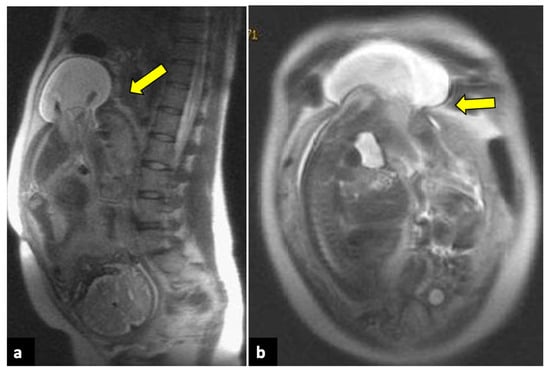

MRI is usually not available in emergency settings. However, it can be useful for further evaluating equivocal findings seen with other techniques and for characterising an underlying ovarian mass [26]. If haemorrhagic infarction is present, the involved ovary shows a T1 hyperintense signal during MRI, with low or without contrast enhancement, and can show diffusion restriction on Diffusion-Weighted Imaging (DWI) sequences. A T1 thin hyperintense ring, representing methaemoglobin, may also be present. Furthermore, the oedematous twisted pedicle can be seen as a heterogeneous structure with a high T2 signal located between the uterus and the enlarged ovary (Figure 3) [28,29].

Figure 3.

Left ovarian torsion in a thirty-nine-year-old patient with acute pelvic pain. Axial T2-weighted (a) and T1-weighted fat saturated before (b) and after (c) gadolinium MR pelvic images show an enlarged left ovary located in the Douglas pouch (yellow arrows), with and adjacent twisted vascular pedicle (“whirlpool sign”, blue arrow). The ovary presents a peripheral high signal on T1 extending to the pedicle (rim of methaemoglobin) without enhancement upon post-contrast sequences. A large cystic lesion arises from the left ovary with an internal high signal on both T1 and T2 (red arrows) and declivous sediment of low signal on T2, suggestive of a haemorrhagic cyst. The patient underwent a laparoscopic left adnexectomy, and pathology confirmed the diagnosis of ovarian torsion possibly due to the haemorrhagic cyst.